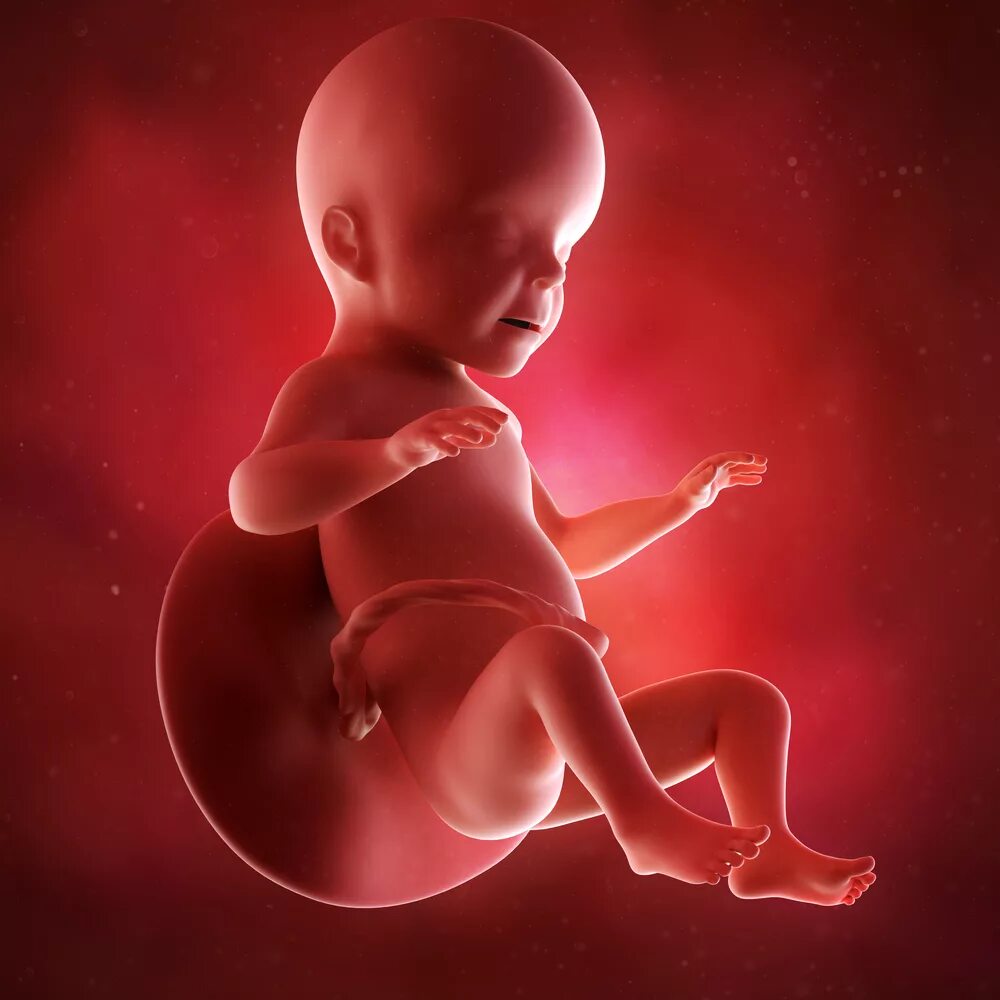

Ощущения 27 неделя